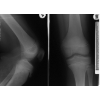

Bei dem Morbus Schlatter handelt es sich um eine Erkrankung, welche bei Jugendlichen im Alter zwischen 14 bis 16 Jahren abläuft. Es handelt sich um eine Verknöcherungsstörung des Ansatzbereiches der Kniescheibensehne am Schienbeinkopf. Der Ansatzbereich der Sehne verwächst nicht mit dem Schienbein, so daß hier ein isolierter Knochenkern bestehen bleibt.

Die Diagnose wird gestellt durch den typischen lokalen Untersuchungsbefund und ein Röntgenbild.

• Schlatter